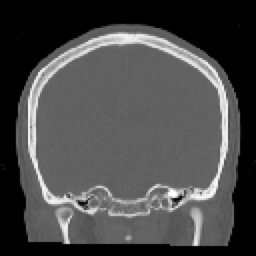

HUESO FINO (5) 129 images

HUESO FINO COR (13) 90 images